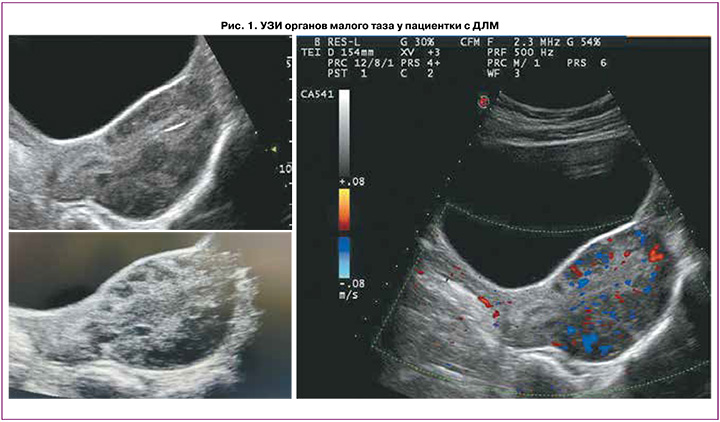

Пациентке выполнено УЗИ органов малого таза на 10-й день менструального цикла (рис. 1). Обнаружено: матка расположена срединно, положение anteflexio, контуры ровные, четкие. Размеры матки: тело 65×51×79 мм, шейка 32×29 мм. Шеечно-маточный угол выражен. Эхо-структура миометрия диффузно неоднородна за счет ячеистой структуры с нечеткими границами. Кровоток при цветном доплеровском картировании усилен. Эндометрий 5,9 мм, однородный. Яичники расположены в углах матки. Правый яичник: 34×15×24 мм. Объем яичника 6,2 см3. Эхоструктура не изменена, содержит фолликулы максимального диаметра 5–6 мм, 6–8 шт. в срезе. Левый яичник: 43×16×22 мм. Объем яичника 8,2 см3. Эхо-структура не изменена, содержит фолликулы максимального диаметра 5–7 мм, 6–8 шт. в срезе. Патологические образования не выявлены. Эхографический диагноз: диффузные изменения миометрия (миоматоз матки?).